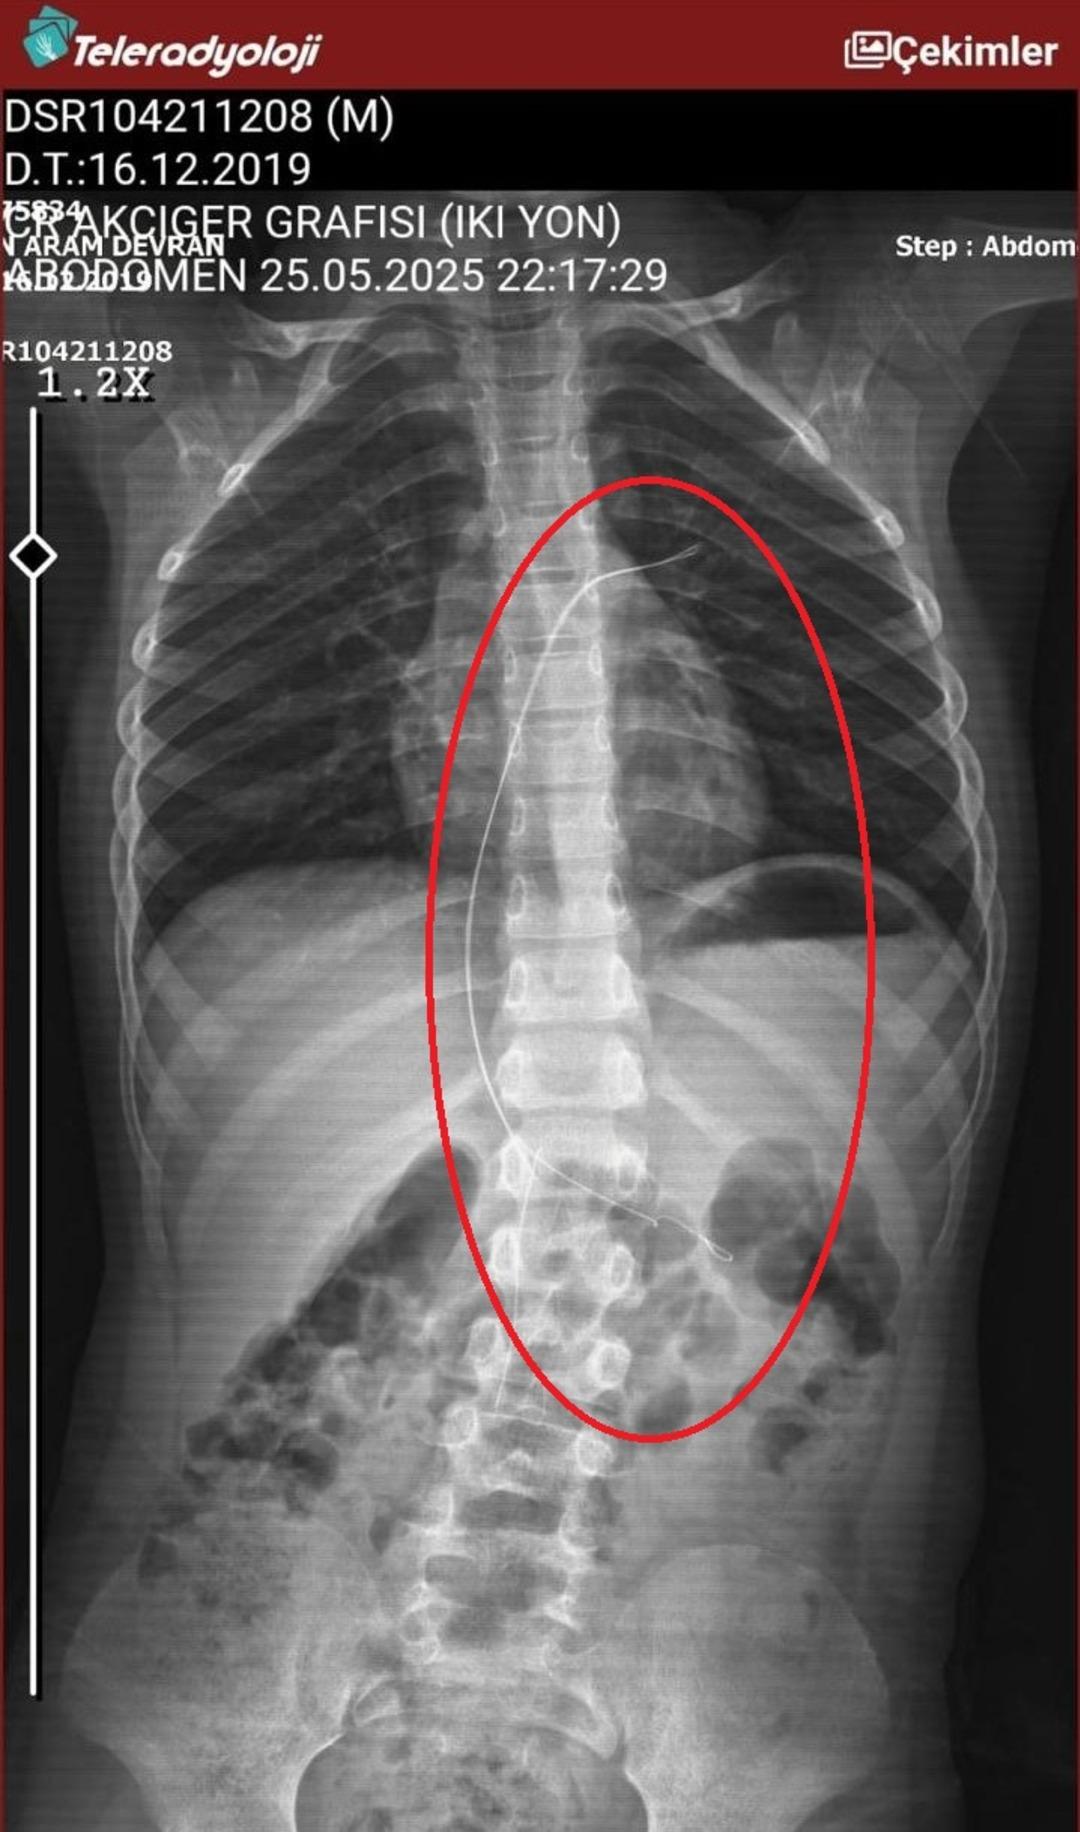

Seamore (37) ve Şaç’ta yaşayan Mehmet Ötün (40), Mayıs ayında bir parça salatalık yuttuktan sonra öksürük ve kusma şikayetleri gözlendiğinde Sernak Eyalet Hastanesine getirildi. Burada, ARAM gövdesinde yarıçap X ve manyetik rezonans görüntüleme unutuldu. Diyarbakir Gazi Yeşargil eğitim ve araştırma hastanesi jinekoloji ve ilave ARAM çocuk binasına yönlendirildi, 18 santimetrede 5.5 saatlik riskli ameliyat kaldırıldı. Postoperatif araştırmalarda, kateter kalp kapakına ve karaciğere zarar vermeye kararlıydı.